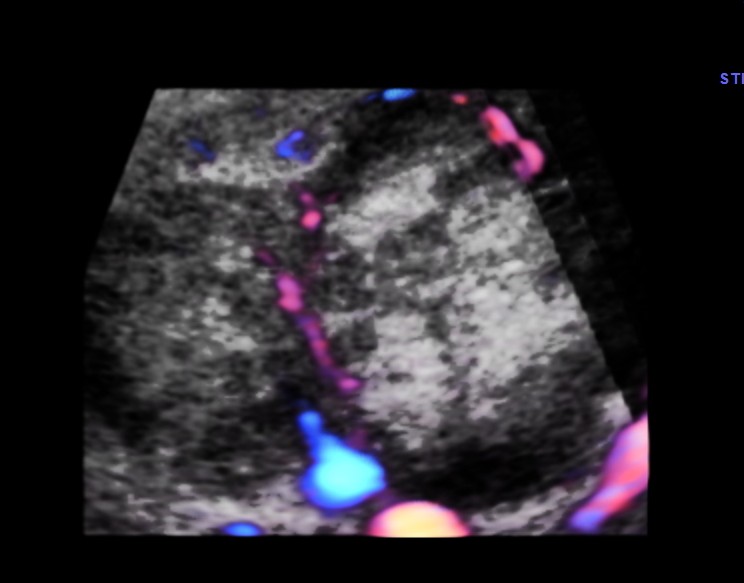

His liver showed multiple secondaries .

secondaries show target appearance or bird’s eye view of mexican hat appearance